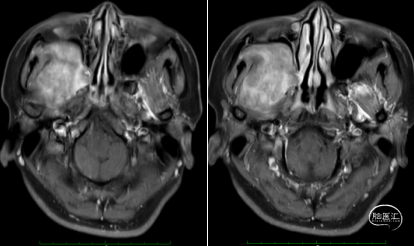

检查所见:鼻窦T1WI、T2WI、DWI图像及动态增强薄层扫描图像示:右侧颞下窝内可见占位,呈T1WI稍低、T2WI高信号,大小约3.5cmx5.5cmx5.6cm(左右x前后x上下),DWI呈高信号,增强扫措可见不均匀强化,边界尚清晰,右侧置外肌正常形态未见。占位部分凸向右侧上颌窦内。左侧上颌窦、双侧额窦、双侧筛窦、蝶窦形态、结构正常,气化良好。鼻道形态正常,鼻中隔未见偏曲,鼻甲粘膜未见增厚。扫描范围内颅底及颌面部软组织未见异常。扫描范围内脑实质未见异常。

检查结论/诊断:右侧颞下窝占位,神经源性肿瘤可能。